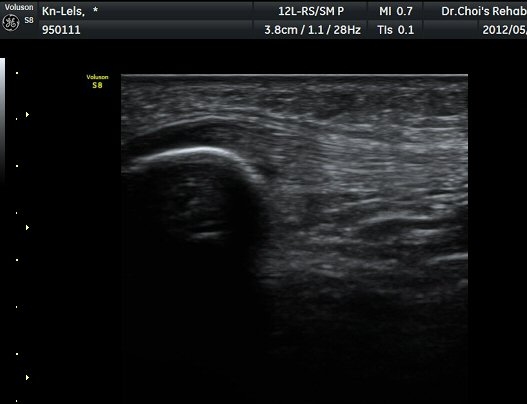

½½°³°ñ¾Æ·¡ ÈûÁÙ Á¾´Ü¸é°Ë»ç¿Í Ⱦ´Ü¸é°Ë»ç¿¡¼­ ÈûÁÙÀÇ ºñÈİ¡ °üÂûµÇ°í(±×¸² 3, 4).

ÈûÁÙÀÇ ºñÈÄ´Â °ÇÃø(±×¸² 5)°ú ºñ±³ÇÏ¸é ¶Ñ·ÈÇϰí, ÆÄ¿öµµÇ÷¯°Ë»ç¿¡¼­ ÈûÁÙ³»¿¡

Ç÷·ùÁõ°¡µµ È®ÀδϵȴÙ(±×¸² 6, 7).